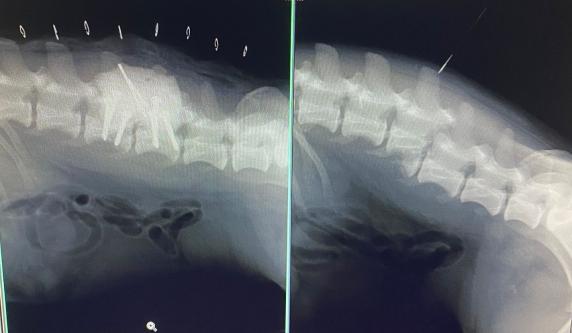

SIDNEY 2280908 male, 25.10.2022., in the shelter since 27.11.2023., from streets of the village where he was hit by a car, his spine was injuried.  He is a miracle dog! Becuase he was operated, and he walked with wheelchair, but now he walks by himself and doesn't need wheelchairs anymore! He just cannot control pipi and kaka by himself.  He is very loyal and attached, loves attention and people, loves cuddles, and to be held in the arms. He adores to play with balls, and ball was the biggest motivation for him to start to walk. He is good with other dogs. Foster home Alex, and she can say more about him.  Cca 35cm